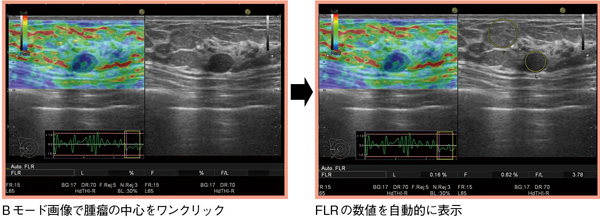

従来の手動計測では,(1)最も安定した時相でエラストグラフィをフリーズする,(2)Bモード画像上で腫瘤のROIを設定する,(3)脂肪のROIを設定すると,FLRが表示されるという複数のステップが必要となる。これに対し,Assist Strain Ratioでは,静止画でBモード画像の腫瘤の中心をワンクリックするだけでFLRの数値が表示される(図3)。

図3 Assist Strain Ratioによる自動計測